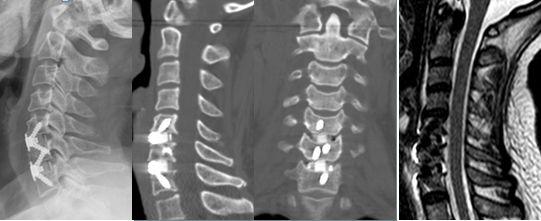

四、颈椎前路微创精准减压融合 或椎间盘置换术

对于部分颈椎患者,需要进行椎间盘彻底切除,并进行融合,部分患者可以保留颈椎活动,行椎间盘置换手术,这类微创手术切口为4厘米左右,出血50-100毫升。

典型案例

黄某,女,39岁,颈痛伴左上肢放射痛及麻木感1年,诊断为神经根型颈椎病。行颈5-6椎间盘切除减压、人工椎间盘置换术。

颈5-6人工椎间盘置换术后,颈椎手术节段运动可以继续保留。

微创前路颈椎椎间盘切除减压融合固定术后,切口仅需4厘米,出血约50-100毫升,术后脊髓压迫彻底解除。